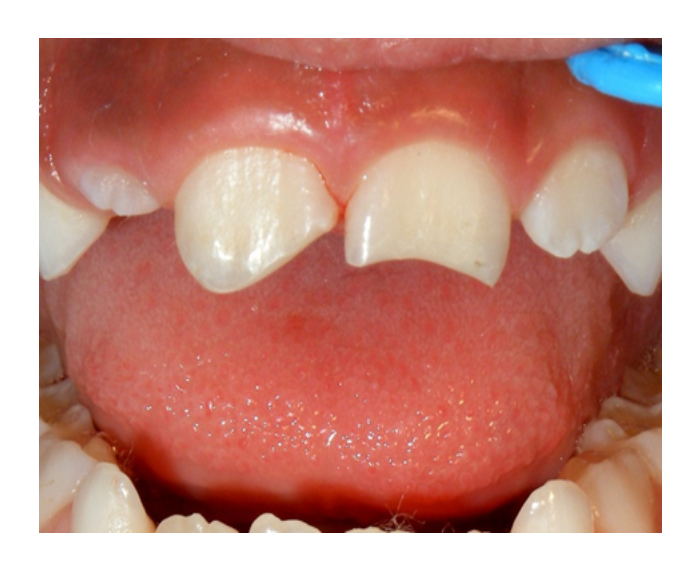

Mordida Cruzada anterior unidental